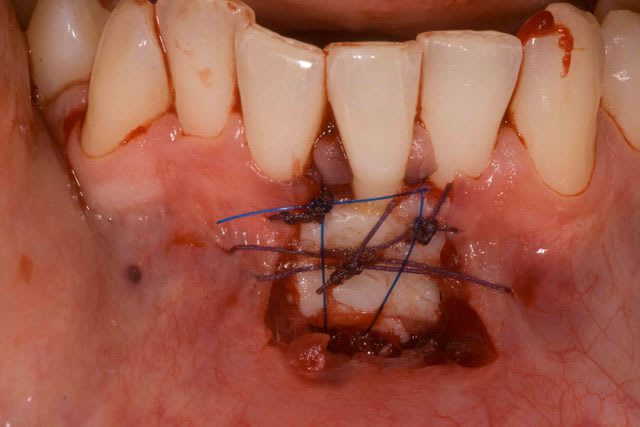

Bon bein voil c'est fait .

Préparer le lit reveveur ok

Le prelevement et la préparation du greffon c'est le plus facile

La ou j'ai eu le plus de difficulté c'est au moment de la mise en place du greffon. Meme en y mettant tout mon courage et ma volonté et du fils 5/0 j'ai pas reussi a suture le lambeau aux papilles . Conclusion il est descendu ... Sinon la freinectomie a pu etre fait sans probleme, lambeau bien plaqué et immobile .

Pour la cicatrisation je croise les doigts.

J'anticipe un peu vos questions :

Pourquoi 2 types de fils ?

j'utilise le 4/0 vicil pour les points facile a mettre en place (aiguille plus grosse et sutures faciles) . Le 5/0 avec sa petite aiguille pour le points plaqué car je n'ai pas le choix .

D'ailleurs le 5/0 prolene c'est vraiment de la merde... il a une memoire de forme et reste embobiné.

Pourquoi ne pas recouvrir toute la racine?

Impossible de suturer au papilles malgres tout mes efforts :/ . La greffe est legerement descendu

Loin de penser que tout soit nikel j'attend vos critiques constructive, surtout celle d'olivier et ceramik :) .

La 2ieme photos correspond au dessin final du lambeau